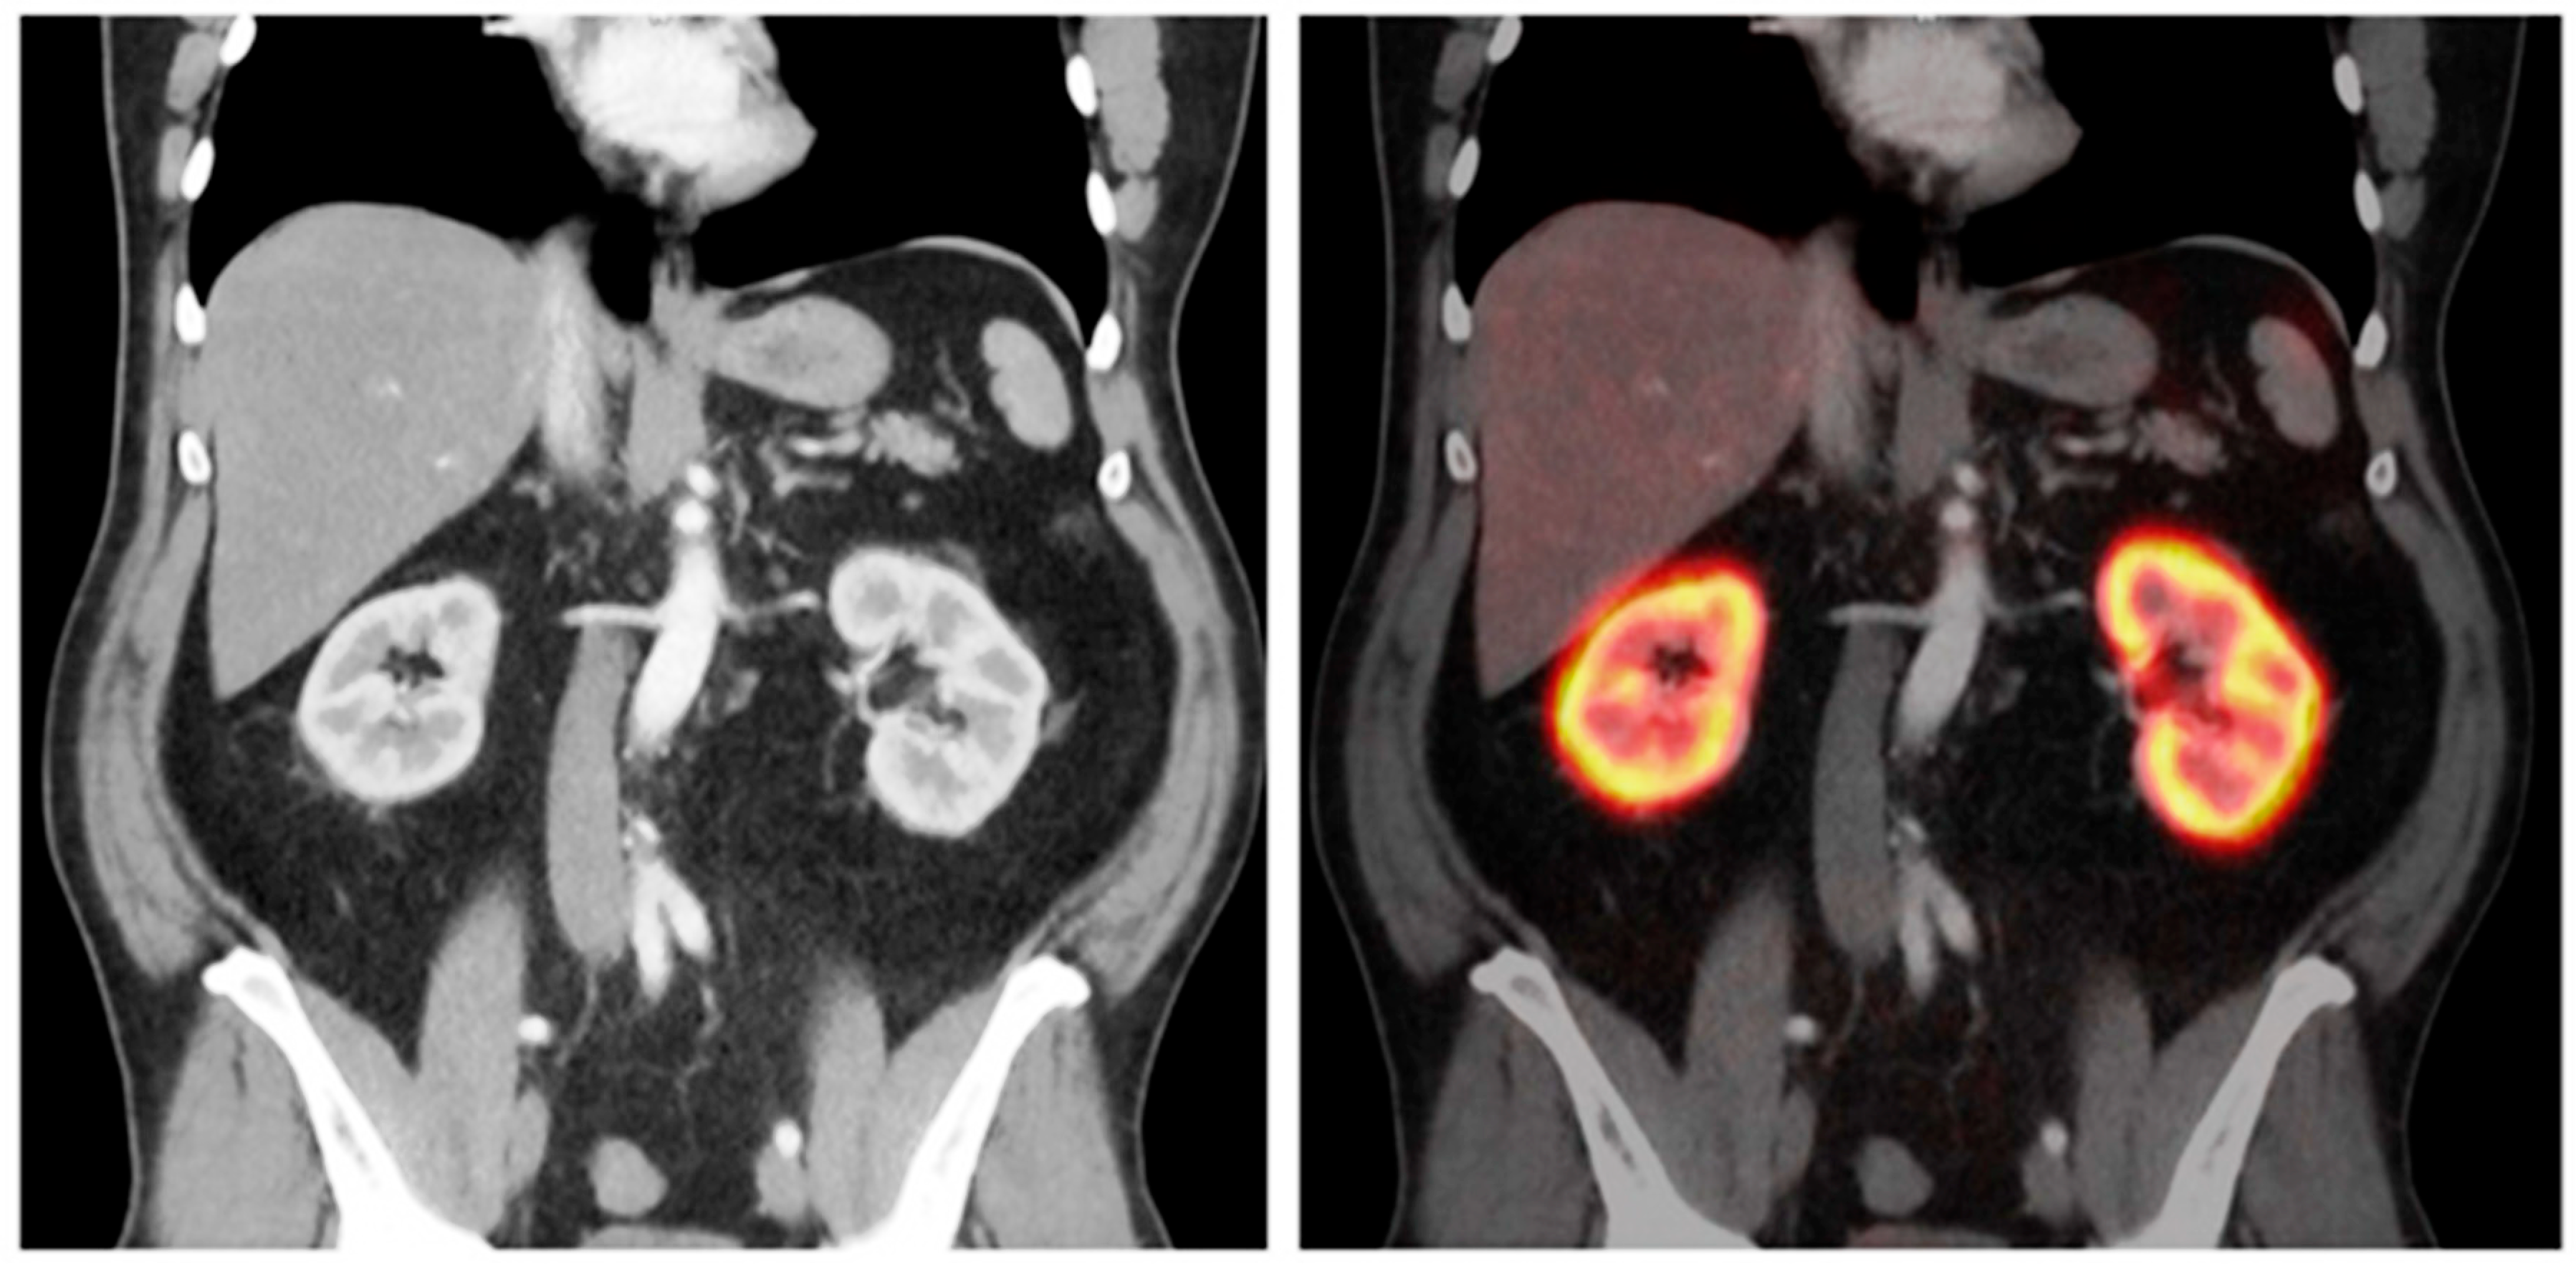

4.1. 68Ga-Labelled Radiotracers for Renal Functional Imaging

4.1.3. 68Ga-PSMA-11